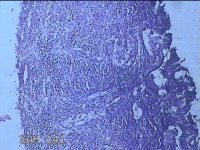

宫颈息肉

性别

女

年龄

36岁

临床诊断

一般病史

阴道流血42天。

标本名称

大体所见

灰白暗红色肿物3.3x2.8x0.3cm一个,表面糜烂,切开肿物呈实性,切面灰白暗红色,质软。